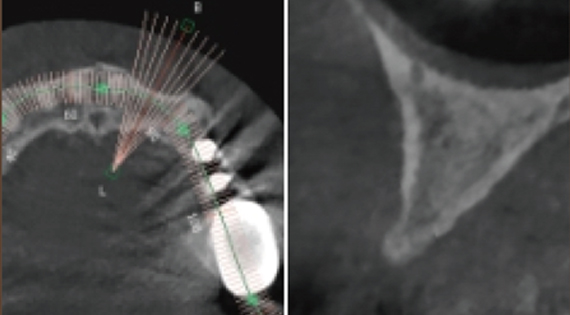

In the case of bone graft(narrow bone width), the bone width can

be expanded using the curvature of the cortical bone and implant

placement is possible without bone graft.

2. Forming minimal implant hole